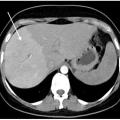

Syndrome de Budd-Chiari

Le syndrome de Budd-Chiari (SBC) est une affection rare caractérisée par une obstruction du drainage veineux hépatique, commençant au niveau des veinules hépatiques jusqu’à la partie terminale de la veine cave inférieure. Il peut se manifester par un tableau d’hépatite fulminante, notamment en cas d’obstruction complète des trois…

La thrombose de la veine porte (TVP) se caractérise par l’obstruction, le plus souvent par un thrombus, de la veine porte et/ou de ses branches portales (droite et/ou gauche). Cette obstruction peut être partielle ou complète, récente (moins de six mois) ou chronique (plus de six mois) et peut également affecter les vaisseaux…